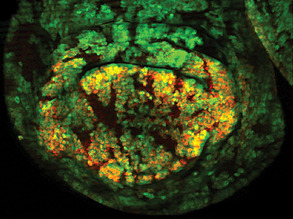

Crafting Kidneys

23